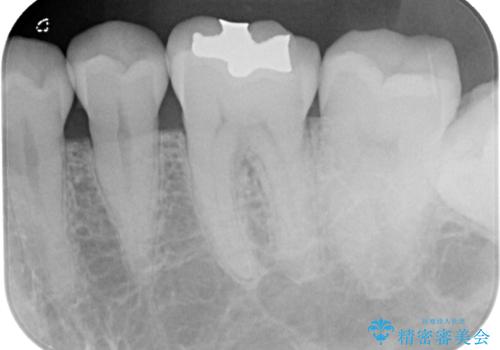

精密検査を行ったところ、上顎左側第二小臼歯のインレー(詰め物)が欠け、その内部に虫歯が進行している状態でした。幸いにも虫歯は神経まで達しておらず、神経を残した治療が可能と判断しました。

まず、虫歯を丁寧に除去。

欠損範囲が大きかったため、オールセラミッククラウンによる補綴治療を行いました。